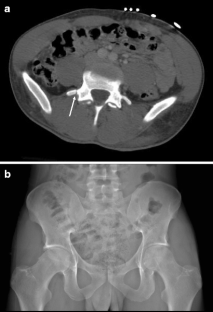

Fig. 1

Fig. 2

Fig. 3